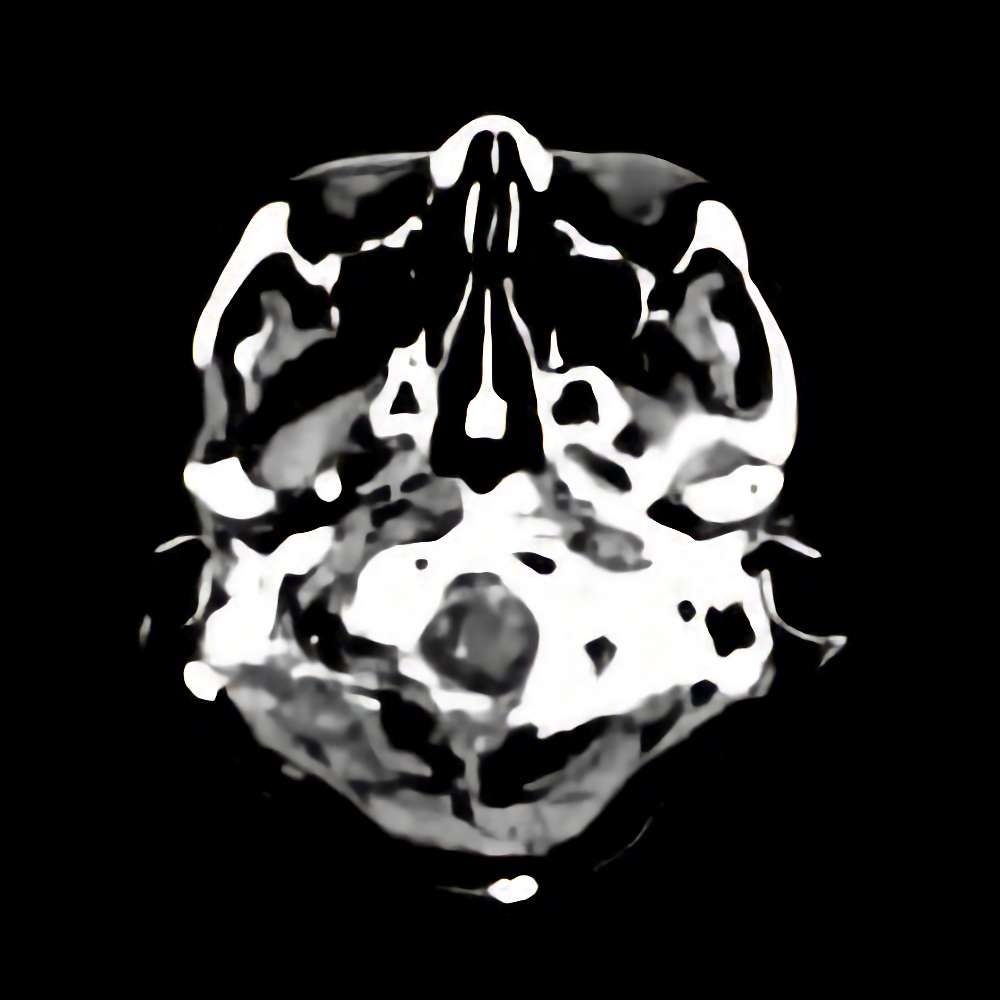

脳腫瘍

(大後頭孔部)

断層撮影

手術前1

No.’13_151 手術前1